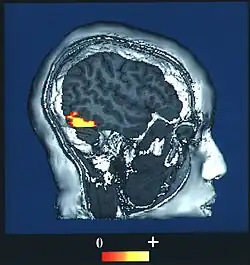

Brain imaging studies typically show a great deal of activity in an area of the temporal lobe known as the fusiform gyrus, an area also known to cause prosopagnosia when damaged (particularly when damage occurs on both sides). This evidence has led to a particular interest in this area and it is sometimes referred to as the fusiform face area (FFA) for that reason.[10]

The fusiform face area (BA37— Brodmann area 37) is located in the lateral fusiform gyrus. It is thought that this area is involved in holistic processing of faces and it is sensitive to the presence of facial parts as well as the configuration of these parts. The fusiform face area is also necessary for successful face detection and identification. This is supported by fMRI activation and studies on prosopagnosia, which involves lesions in the fusiform face area.[34][35][36][37][38]

During face perception, major activations occur in the extrastriate areas bilaterally, particularly in the above three areas.[34][35][38] Perceiving an inverted human face involves increased activity in the inferior temporal cortex, while perceiving a misaligned face involves increased activity in the occipital cortex. No results were found when perceiving a dog face, suggesting a process specific to human faces.[41] Bilateral activation is generally shown in all of these specialized facial areas.[42][43][44][45][46][47] However, some studies show increased activation in one side over the other: for instance, the right fusiform gyrus is more important for facial processing in complex situations.[36]

One study used BOLD fMRI mapping to identify activation in the brain when subjects viewed both cars and faces. They found that the occipital face area, the fusiform face area, the superior temporal sulcus, the amygdala, and the anterior/inferior cortex of the temporal lobe all played roles in contrasting faces from cars, with initial face perception beginning in the fusiform face area and occipital face areas. This entire region forms a network that acts to distinguish faces. The processing of faces in the brain is known as a "sum of parts" perception.[49]